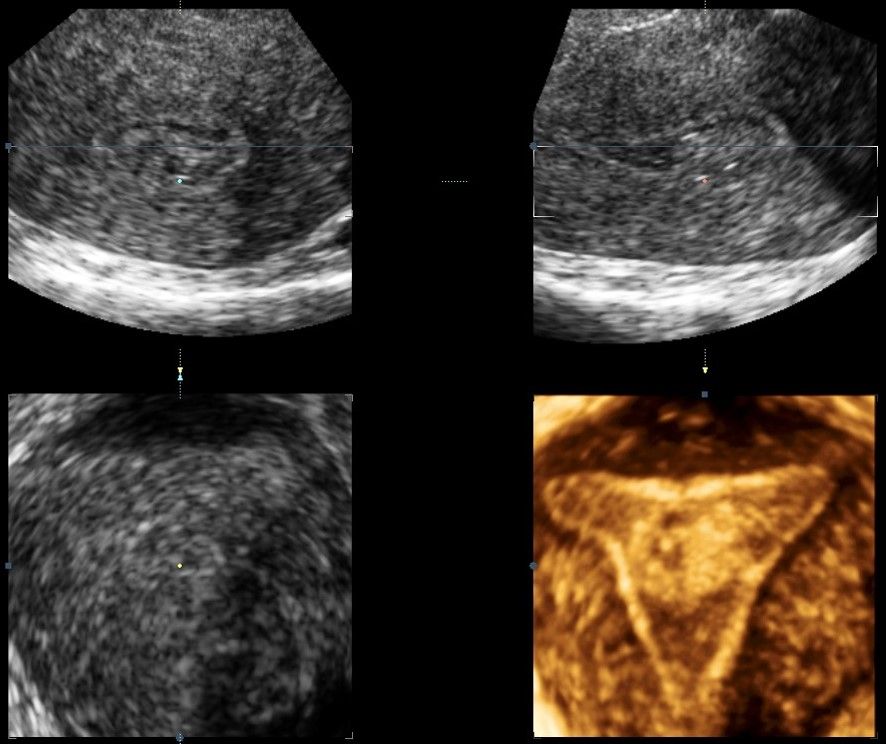

Современные экспертные УЗИ сканеры дают возможность проводить исследования всех органов в 3D. Это позволяет, используя полученный массив данных, получать диагностические сечения в любой плоскости, недоступной для обычного 2D УЗИ. Наиболее интересной является фронтальная. Например, визуализация полости матки. Диагностическая возможность выявления пороков развития превосходит все другие методы (рентгеновские и МРТ). Метод также позволяет уточнить положение ВМК (спирали) в полости матки, расположение миоматозных узлов, расположение плодного яйца на малых сроках, полипов. Сегодня современное экспертное ультразвуковое исследование невозможно без использования 3D УЗИ.